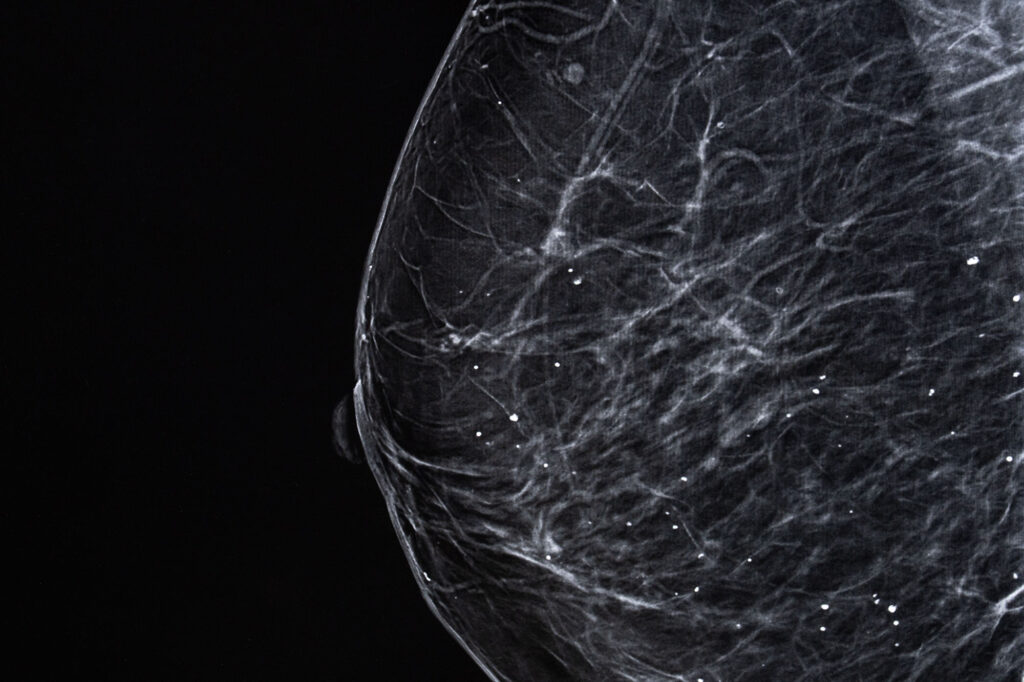

- Dans 70 % des cas, on peut réaliser un "traitement conservateur" appelé "tumorectomie" (ablation de la tumeur). Elle est indiquée dans de nombreux cas de cancer du sein dépistés précocement.